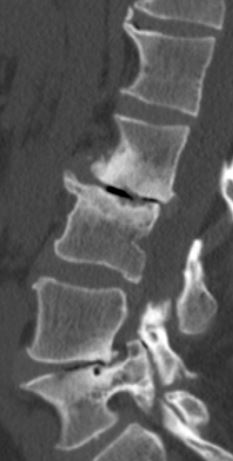

i am the bionic woman, iron woman, titanium broad, i don't know quite yet hopefully i don't break any of the rods or pull any screws...but heres the before and after xrays....

before: lateral scoliosis

lumbar spine 1 scoliosis.JPG

and rotatory scoliosis

right bending.JPG

with bad discs and bone spurs

bone spur and disc degeneration L23.JPG

i am pretty darned close to 0 degrees on the scoliosis!!!! and my spine isn't twisted anymore either! it feels totally different to walk, sit, stand, basically to do anything, but that's okay! the square things in the after xrays are cages to replace the discs that were removed.

been doing all my wussy stretching exercises....still feeling really timid and tender around L2, which is the one that is worst off to the left side in the first xray. they really had to crank that one back into position. i also met some very very happy medical students LOL. they thought it was "so cool and totally awesome" (quote-scary enough) that they could see a laminectomy and help put me back together again (apparently everything twisted and they needed hands to hold things in place so they're stop twisting.....um. LOL.

so they removed the backs off the vertebrae at L2 L3 L4 and L5 it looks like from the xrays. took out all the facet joints (the bars are where they would be)....so that freed up all the pinched nerve roots and took the pressure off my spinal cord.